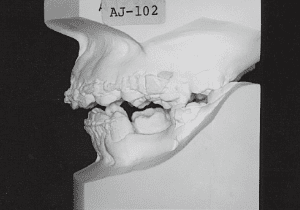

Documents to bring: Dental model at initial visit

3 Year and month unknown Original